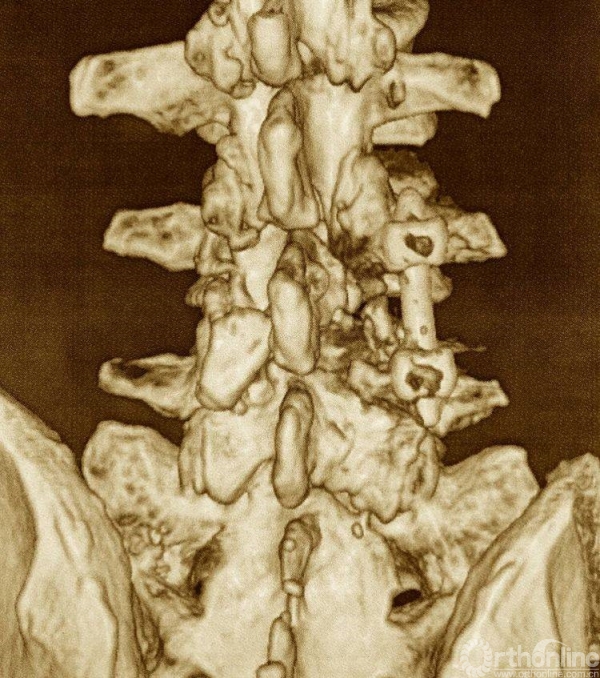

术后资料:

椎管狭窄减压较术前容积扩大

矢状位融合器、植骨位置及滑脱复位情况

术后三维CT资料